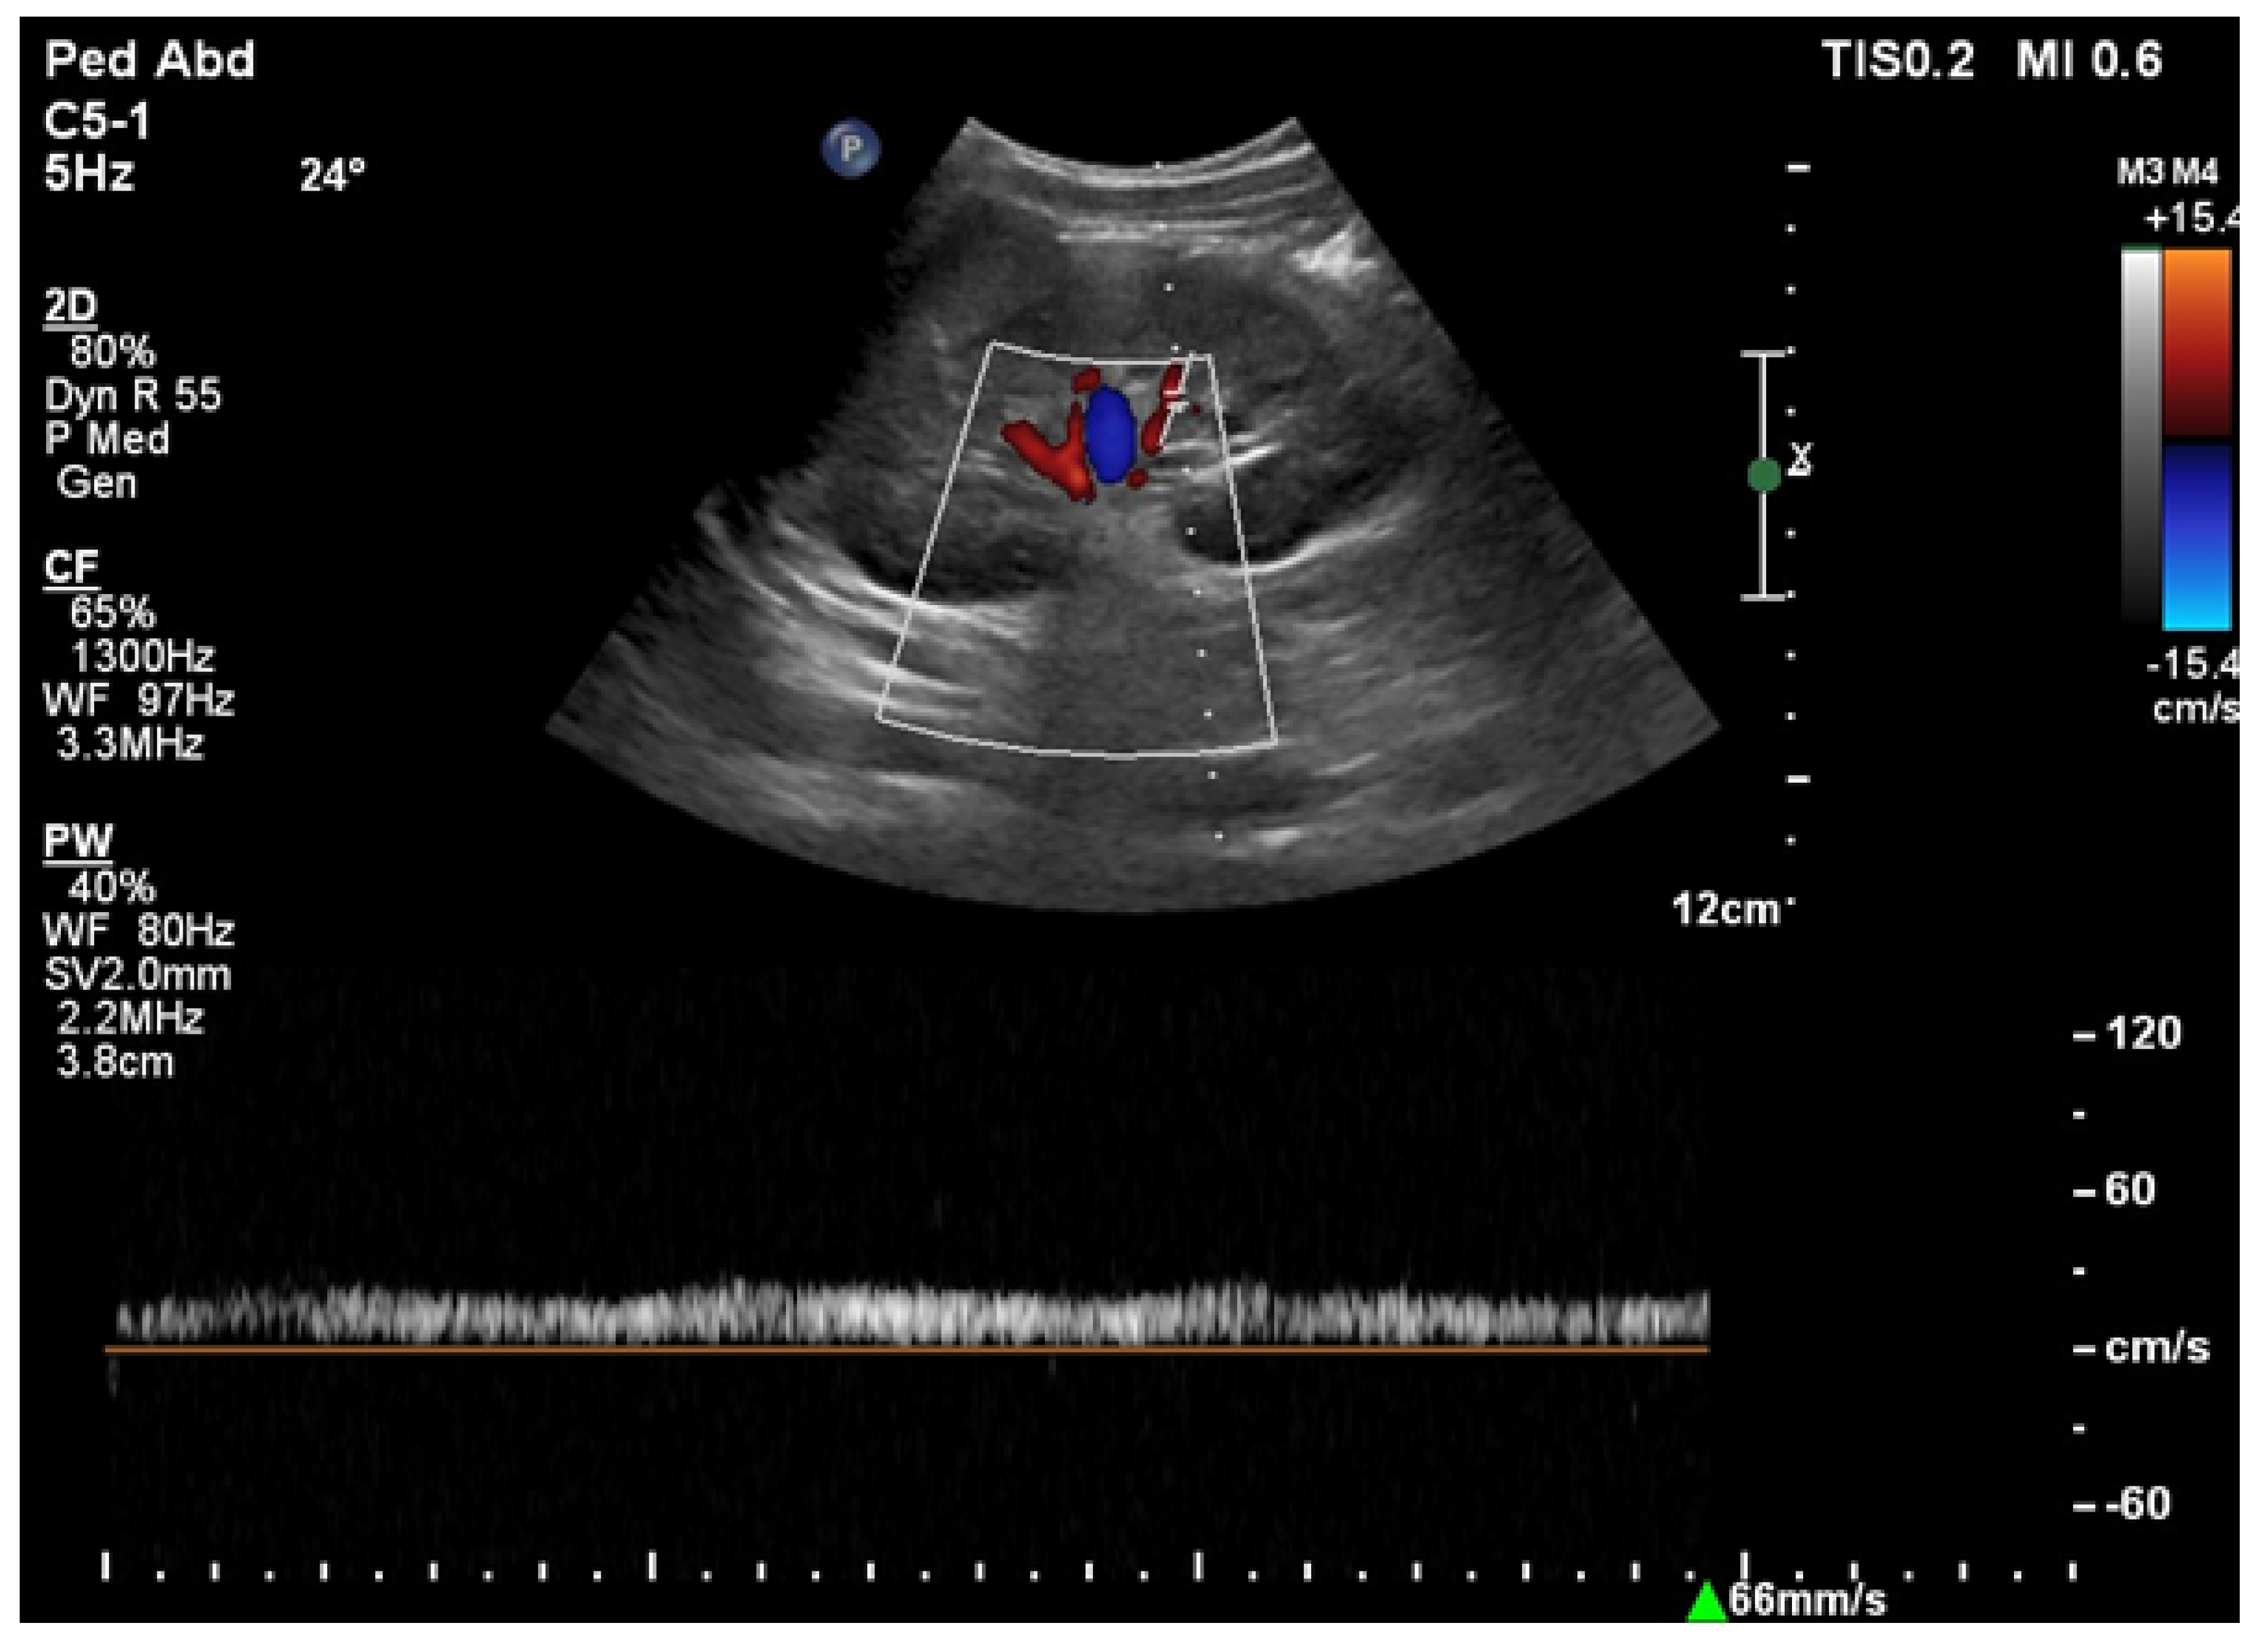

6.1. Ultrasound

- Drelich-Zbroja, A. Polish Society of Ultrasonography Standards—Update: Ultrasound Examination of Renal Arteries. J. Ultrason. 2014, 14, 297–305. [Google Scholar] [CrossRef]

- Stryczyński, Ł. Doppler ultrasound of renal arteries. Arter. Hypertens. Pract. 2022, 8, 186–199. [Google Scholar]

- Saida, K.; Kamei, K.; Hamada, R.; Yoshikawa, T.; Kano, Y.; Nagata, H.; Sato, M.; Ogura, M.; Harada, R.; Hataya, H.; et al. A simple, refined approach to diagnosing renovascular hypertension in children: A 10-year study. Pediatr. Int. 2020, 62, 937–943. [Google Scholar] [CrossRef]

| Normal Value | Parameter |

|---|---|

| 100 cm/s * | PSV (peak systolic velocity) in artery trunk |

| 0.8–1.0 | RAR (renal aortic ratio) in artery trunk |

| ≤70 ms | AT (acceleration time) in intrarenal branches |

| 0.5–0.8 | RI (resistance index) in intrarenal branches |

| 0.78–1.33 | PI (pulsatility index) in intrarenal branches |

| >3 m/s2 | AI (acceleration index) in intrarenal branches |